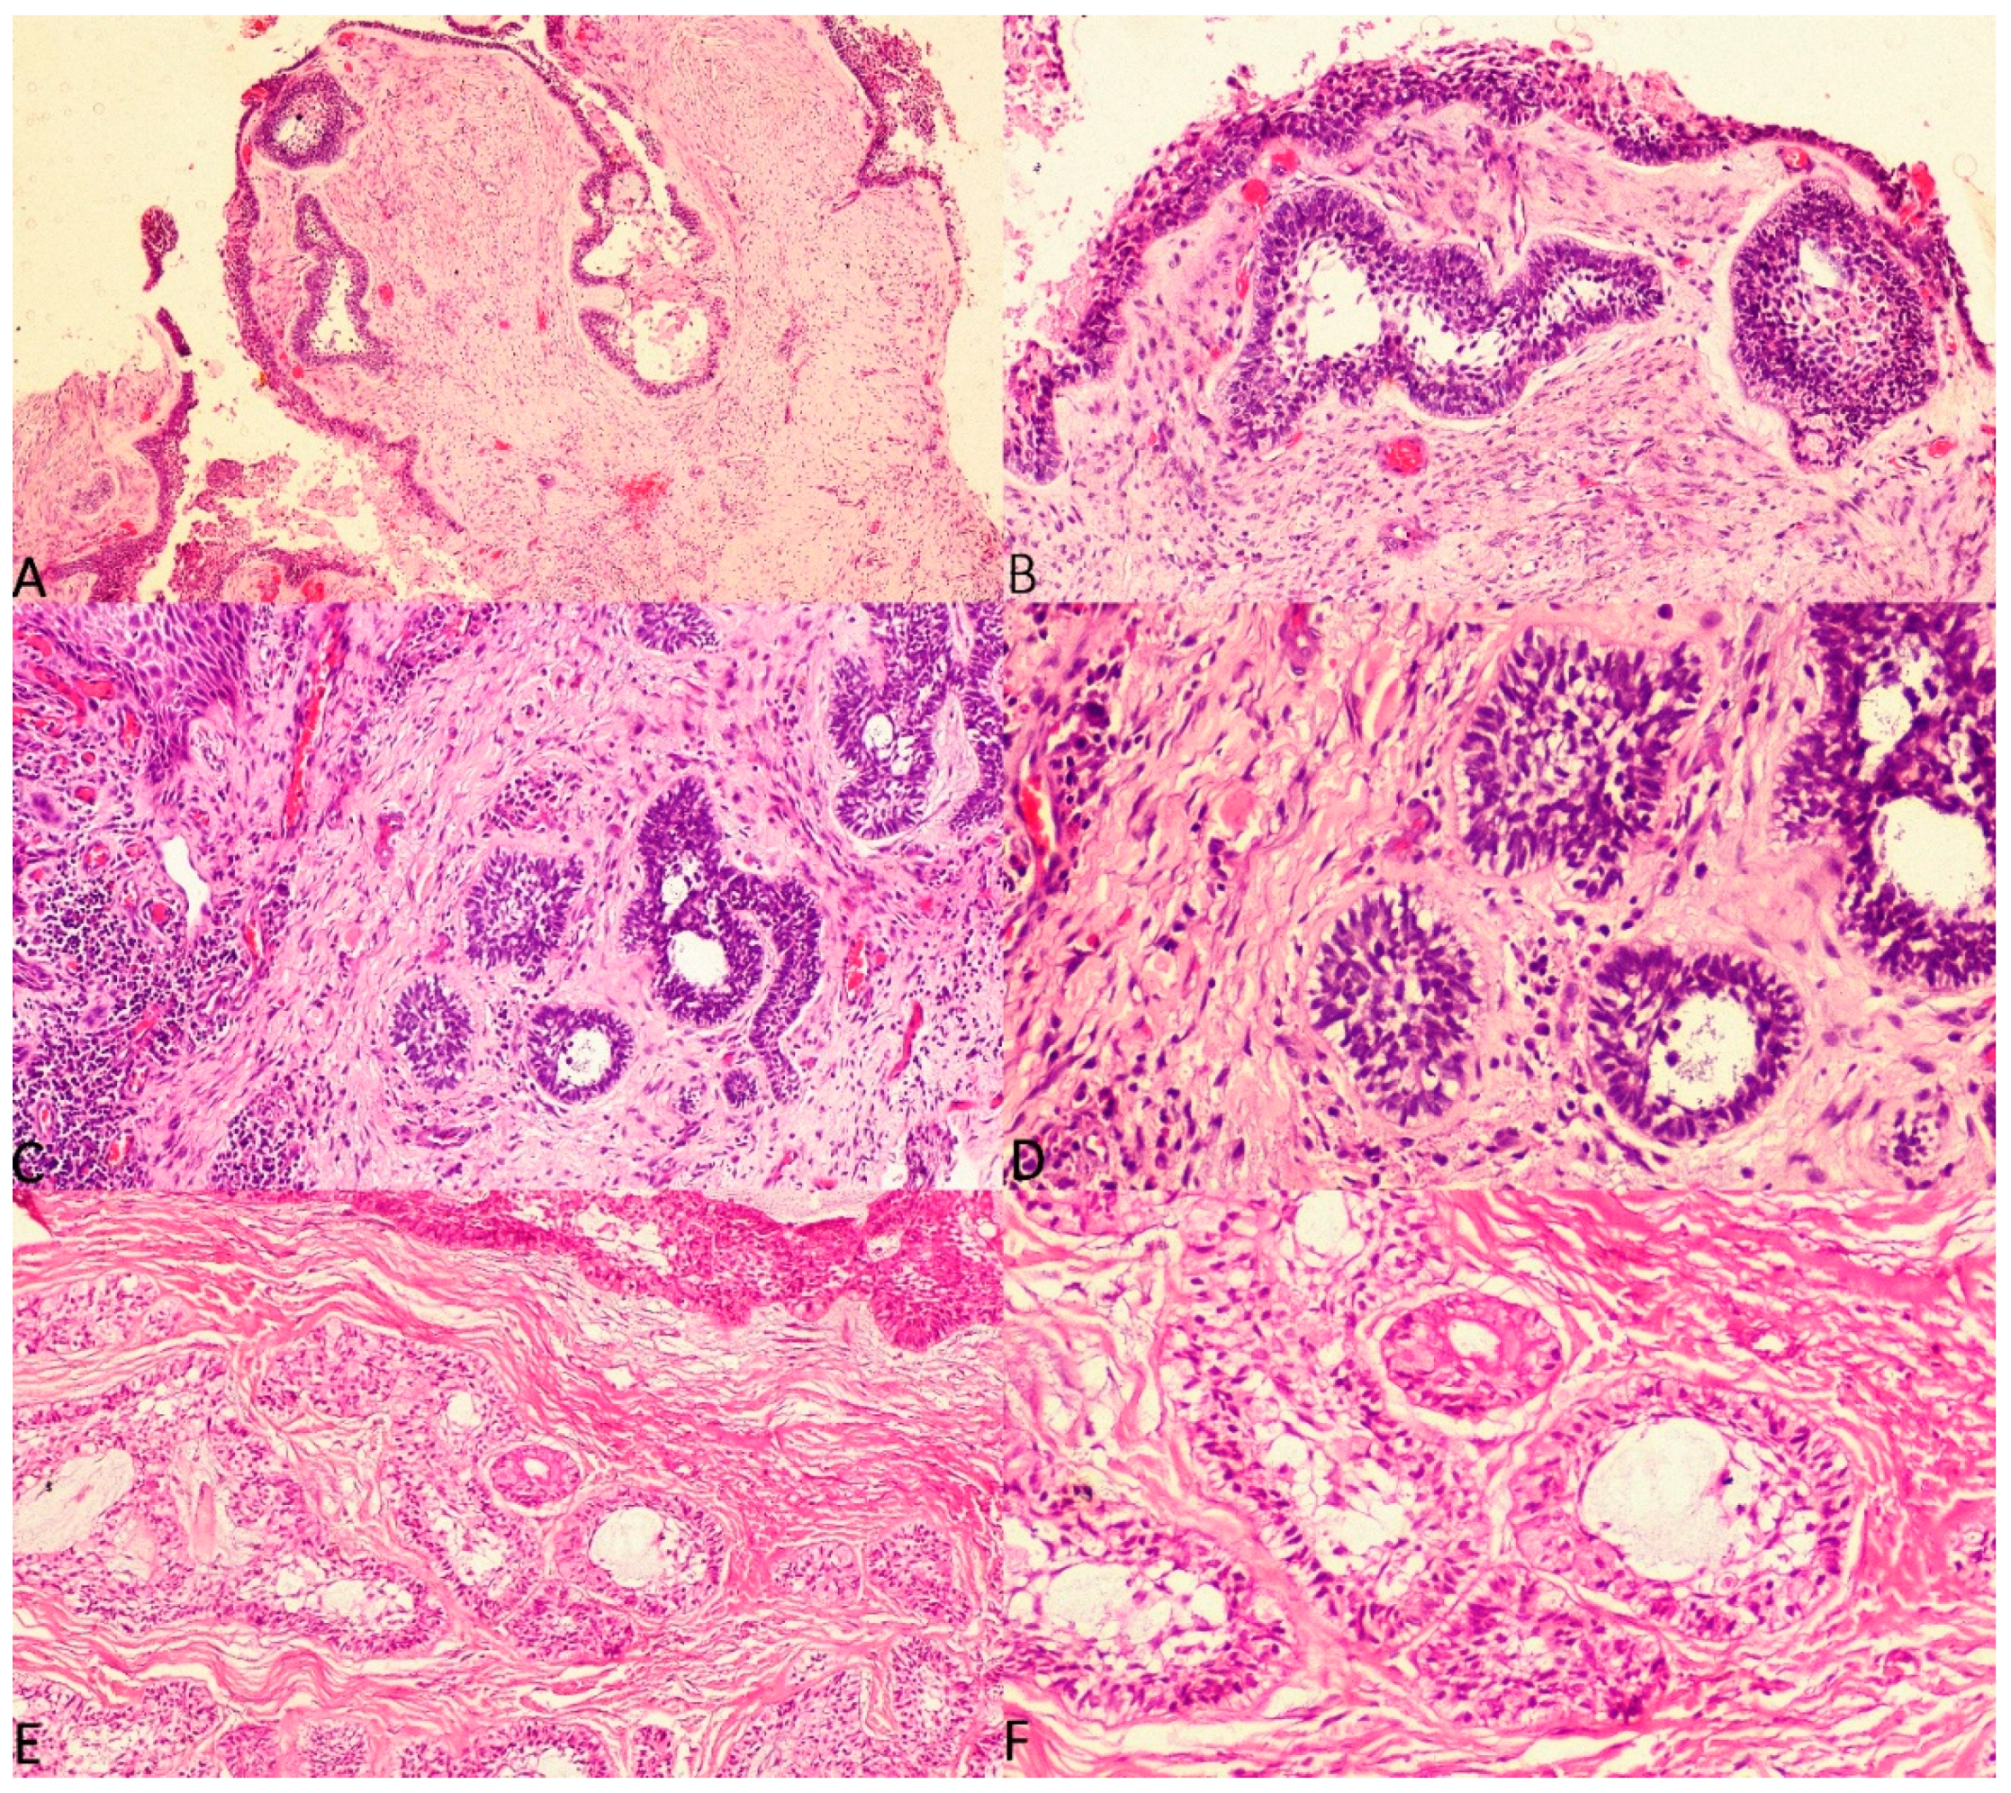

The current study considered three histologic subtypes of UA and attempted to draw an association between hyalinisation and recurrence aided by clinicopathological correlation. The SOH was compared between the subtypes of UA (UA-IL (Figure 3A–F), UA-L (Figure 4A–F) and UA-M); it was observed that a significant statistical correlation existed between SOH and recurrence in UA-M type (p = 0.001), Figure 5A–F.

Figure 3. Photomicrographs of haematoxylin and eosin stain. Unicystic ameloblastoma—intraluminal type with absence of SEH, (A) 40×, (B) 100× and (C) 200×. Unicystic ameloblastoma—intraluminal type with prominent SEH, (D) 100×, (E) 200× and (F) 400×.

Figure 4. Photomicrographs of haematoxylin and eosin stain. Unicystic ameloblastoma—luminal type with absence of SEH, (A) 40×, (B) 100× and (C) 200×. Unicystic ameloblastoma—luminal type with prominent SEH, (D) 100×, (E) 200× and (F) 400×.